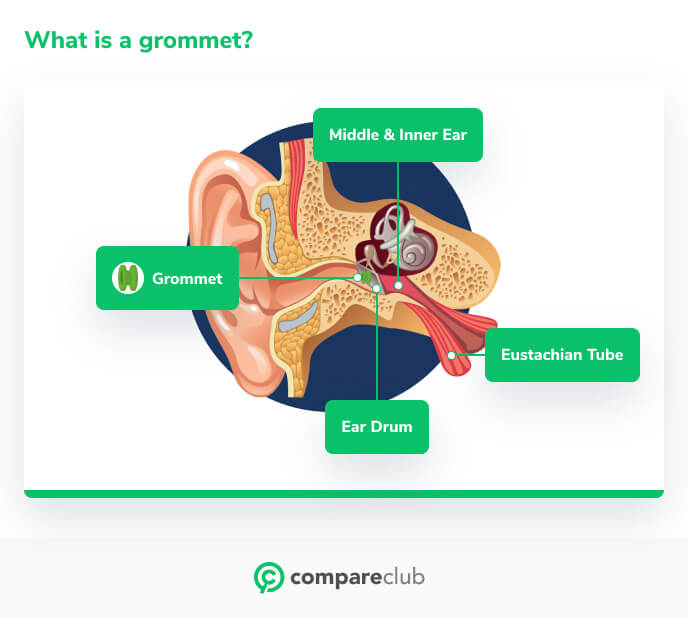

What are grommets cheap

What are grommets cheap, Grommets Mr Daniel Tweedie Consultant Paediatric ENT Surgeon cheap

What is a grommet ent4kids cheap, Grommets ENT Info cheap, Grommets Mr Daniel Tweedie Consultant Paediatric ENT Surgeon cheap, Grommets KidsHealth NZ cheap, Grommets KidsHealth NZ cheap, Description of operation for grommet ventilation tube insertion cheap, Grommets A decision making aid for parents ENT UK cheap, Grommets aarontrinidade cheap, Glue Ear Middle Ear Infections and Grommets Dr Sean Flanagan cheap, Ear Grommets ENT Clinic Sydney cheap, Grommets Adelaide Specialist ENT Surgeon Paul Varley ENT cheap, Ear Grommets ENT Clinic Sydney cheap, Grommets healthdirect cheap, Grommet Insertion Child Parkside Hospital cheap, Treatment of glue ear with grommets Great Ormond Street Hospital cheap, Grommets North View ENT Dr Sebastian Ranguis ENT Surgery cheap, Grommets Children s Health Queensland cheap, Grommets cheap, Grommets Ear Nose Throat Newcastle cheap, What are Grommets and how do they work Dr. Shalina Ray cheap, Grommets And The Benefits of Using Them cheap, Middle ear ventilation tubes grommets Dr Bridget Clancy ENT cheap, Grommets Mr Daniel Tweedie Consultant Paediatric ENT Surgeon cheap, Glue Ear Grommets Western ENT cheap, Grommet Insertion Surgery India Cost Grommet Insertion Surgery Abroad cheap, James Rainsbury Plymouth ENT specialist consultant Private cheap, How much does ear grommet surgery cost in Australia cheap, Grommets for glue ear treatment Essex London ENT cheap, Grommets Ear Nose Throat Newcastle cheap, Water precautions following grommets Dr Jeeve ENT Specialist cheap, All you need to know about grommets You cheap, Sydney Paediatric ENT Surgeon For Ear Grommets MY ENT cheap, Grommets MESHGuides cheap, Grommets aarontrinidade cheap, Grommets ENT Doctor Cape Town Dr Shabeer Ebrahim cheap.

What is a grommet ent4kids cheap, Grommets ENT Info cheap, Grommets Mr Daniel Tweedie Consultant Paediatric ENT Surgeon cheap, Grommets KidsHealth NZ cheap, Grommets KidsHealth NZ cheap, Description of operation for grommet ventilation tube insertion cheap, Grommets A decision making aid for parents ENT UK cheap, Grommets aarontrinidade cheap, Glue Ear Middle Ear Infections and Grommets Dr Sean Flanagan cheap, Ear Grommets ENT Clinic Sydney cheap, Grommets Adelaide Specialist ENT Surgeon Paul Varley ENT cheap, Ear Grommets ENT Clinic Sydney cheap, Grommets healthdirect cheap, Grommet Insertion Child Parkside Hospital cheap, Treatment of glue ear with grommets Great Ormond Street Hospital cheap, Grommets North View ENT Dr Sebastian Ranguis ENT Surgery cheap, Grommets Children s Health Queensland cheap, Grommets cheap, Grommets Ear Nose Throat Newcastle cheap, What are Grommets and how do they work Dr. Shalina Ray cheap, Grommets And The Benefits of Using Them cheap, Middle ear ventilation tubes grommets Dr Bridget Clancy ENT cheap, Grommets Mr Daniel Tweedie Consultant Paediatric ENT Surgeon cheap, Glue Ear Grommets Western ENT cheap, Grommet Insertion Surgery India Cost Grommet Insertion Surgery Abroad cheap, James Rainsbury Plymouth ENT specialist consultant Private cheap, How much does ear grommet surgery cost in Australia cheap, Grommets for glue ear treatment Essex London ENT cheap, Grommets Ear Nose Throat Newcastle cheap, Water precautions following grommets Dr Jeeve ENT Specialist cheap, All you need to know about grommets You cheap, Sydney Paediatric ENT Surgeon For Ear Grommets MY ENT cheap, Grommets MESHGuides cheap, Grommets aarontrinidade cheap, Grommets ENT Doctor Cape Town Dr Shabeer Ebrahim cheap.